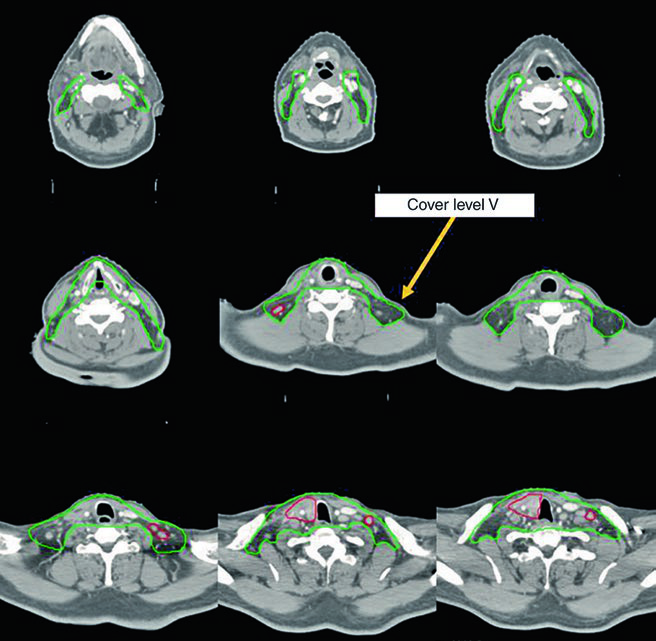

Caso 1 — Carcinoma papilar metastático (Fig. 9.1): Homem de 58 anos com carcinoma papilar metastático de tireoide, submetido a múltiplas ressecções prévias, que se apresentou com recorrência local irressecável e múltiplos linfonodos mediastinais. Recebeu quimiorradioterapia definitiva para prevenir progressão local. O CTV70 Gy (vermelho) abrange a recorrência local e linfonodos mediastinais envolvidos, enquanto o CTV60 Gy (verde) cobre as regiões subclínicas de risco. Este caso exemplifica o cenário de doença recorrente que esgotou as opções cirúrgicas — a radioterapia com dose definitiva é a melhor alternativa para controle local.

Caso 2 — Carcinoma anaplásico irressecável (Fig. 9.2): Mulher de 73 anos com carcinoma anaplásico de tireoide invadindo laringe, traqueia e esôfago. Recebeu quimiorradioterapia definitiva com doxorrubicina concomitante. O CTV70 Gy (vermelho) engloba toda a doença volumosa, e o CTV60 Gy (verde) abrange o risco subclínico. Detalhe importante: o manúbrio, que normalmente não é incluído no volume de risco, foi englobado neste caso específico por conta da doença volumosa anterior agressiva no pescoço. Essa decisão é atípica e deve ser individualizada — não se trata de protocolo, mas de resposta a uma apresentação clínica particular.

Esses dois casos ilustram a versatilidade da IMRT com dose-painting: o plano entrega simultaneamente 70 Gy ao volume de alto risco e 60 Gy ao volume subclínico, sem necessidade de boost sequencial. A escolha de doxorrubicina como quimioterápico concomitante no anaplásico reflete a agressividade dessa histologia e a necessidade de sensibilização ao tratamento, embora as opções sistêmicas tenham evoluído significativamente nos últimos anos.